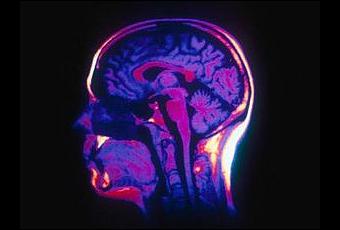

Une consommation régulière et précoce d'alcool et notamment les "ivresses express" (binge drinking) sont devenues un phénomène préoccupant chez les jeunes de la plupart des pays Européens. Les premiers résultats d’études menées chez l’animal et chez l’Homme mettent en évidence des effets délétères à long terme sur le cerveau des adolescents et un risque de dépendance à l’âge adulte.

Le binge drinking, pratique originaire du Royaume-Uni, consiste à absorber une quantité maximale d’alcool en un temps réduit. Au-delà des effets immédiats relativement bien connus, des travaux de recherche récents menés chez l’animal et chez l’Homme montrent des effets à long terme préoccupants. Avec la propagation de ces nouveaux modes de consommation, des conséquences majeures sur la santé sont donc attendues durant les prochaines décennies, notamment une augmentation du taux de mortalité et une recrudescence du nombre d'individus alcoolodépendants.